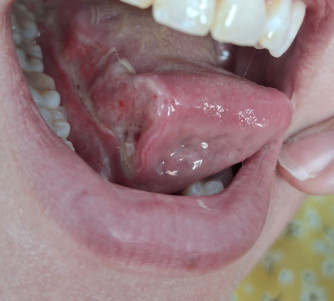

13 juni 2025 ben ik geopereerd aan de plaveiselcelcarcinoom op de tong en de schildwachtklierprocedure is uitgevoerd.

Eenmaal terug op de afdeling ging het best goed. Pijn was minimaal en prima te doen met PCM en Naproxen. Wel veel hoofdpijn door de narcose. Ik had echt de hel verwacht maar dit was echt goed te doen. Praten ging ook best goed. Langzaam en vrij monotoon maar er kwam in ieder geval geluid uit. Heel fijn want dat vond ik toch best spannend. De eerste paar uur durfde ik nog niet de tong te bekijken. Wat zou ik aantreffen? Ze hebben het met een laser weggesneden en vervolgens gehecht. Maar het zag er best oke uit. Ook de hechtingen in de hals zaten netjes in de halslijn. Daar zie je over een tijdje niet meer zoveel van. Maar goed, er moest ook wel weer wat gegeten worden. Wat een spannend moment. Het lukte mij om stukjes brood met jam in stukje van 1cm bij 1cm naar binnen te krijgen en volgens een ritme door te slikken. Na een half uur had ik toch 1 snee brood op! Yes, wat was ik trots!  Veel ijswater en koude thee. Melkachtige producten gaf veel slijmvorming dus die werden even weggelaten. Smootie's waren nog te zuur. Heldere afgekoelde soep deed het ook goed.

Ondertussen ging het herstel thuis best goed. Het eten nam best veel tijd in beslag omdat het vrij langzaam ging. Praten ging best goed. Wel erg wennen dat je een stukje mist. Hij boog wat af naar links en dat probeer je steeds de corrigeren wat natuurlijk niet lukt. Pijn heb ik minimaal gehad. Mijn hals was behoorlijk gezwollen, omvang kalkoen. Maar dit werd in de loop van tijd minder dik en qua kleur trok het weer bij. Doordat ik mogelijk wel wat zenuwen onder de huid zijn geraakt heb ik geen gevoel onder mijn kin.

Toen was het 2 juli, de dag dat de uitslag binnenkwam. Aan het einde van de middag ging de telefoon. De snijmarge van de tong was niet voldoende. Ze hadden verwacht dat de tumor een knobbel zou zijn, de doorsnede was 24mm, het blijkt echter een soort spin te zijn met kleine haartjes die zich verder nestelt. Ze komen bij 1 haartje 2mm te kort van de snijmarge. Echt millimeter werk dus. Als dit het enige zou zijn kun je afwegen om het zo te laten (omdat de snijrand in feite schoon is maar dus niet voldoende) en het vaak te controleren. Echter is er in 1 schildwachtklier toch een uitzaaiing gevonden. Niet schoon dus. Het omliggende gebied in de hals moet dus wederom ook geopereerd worden en verder "schoongemaakt". De arts stond zelf ook te kijken van de uitslag maar zoals hij zelf zegt "Als we nu niks doen staan we over een paar maanden 1-0 achter en is de wedstrijd gespeeld. Nu staan we nog met 1-0 voor en moeten we er voor gaan.... " Dat betekent dat de operatie in een iets kleinere variant weer opnieuw moet voor de tong en er volgt een halsklierdissectie aan de rechterkant. Behoorlijk k#t want de laatste dagen ging het herstel echt wel de goede kant op en de kans op uitzaaiingen was erg klein. Het is en blijft eng dat er zoiets in de lichaam kan groeien wat er niet hoort. De arts verwacht de operatie opnieuw te kunnen uitvoeren op vrijdag 18 juli. Maar ook dit onder voorbehoud. Hopelijk hoor ik volgende week de definitieve datum. Deze zagen we niet helemaal aankomen, de bubbels lagen al klaar in de koelkast en de champagne glazen waren gepoetst. Deze teleurstelling moeten we weer even een plekje gaan geven  en ons weer oppeppen voor de volgende operatie .